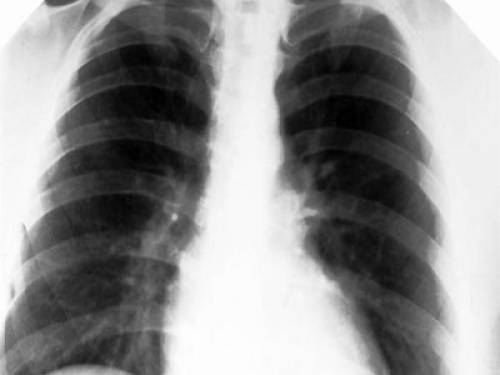

如果是屬於以上四類人群的,最好每年都做一次肺癌篩查。目前低劑量螺旋CT是國際上通用的篩查早期肺癌的金標準。相比普通CT,低劑量螺旋CT檢查所受的放射線劑量要小很多,大概是六分之一,而準確性很高,能查出兩毫米以上的微小結節,這樣發現的肺癌,大概90%以上都是早期了。早期肺癌,首選手術治療,甚至微創就可以實現良好的效果。